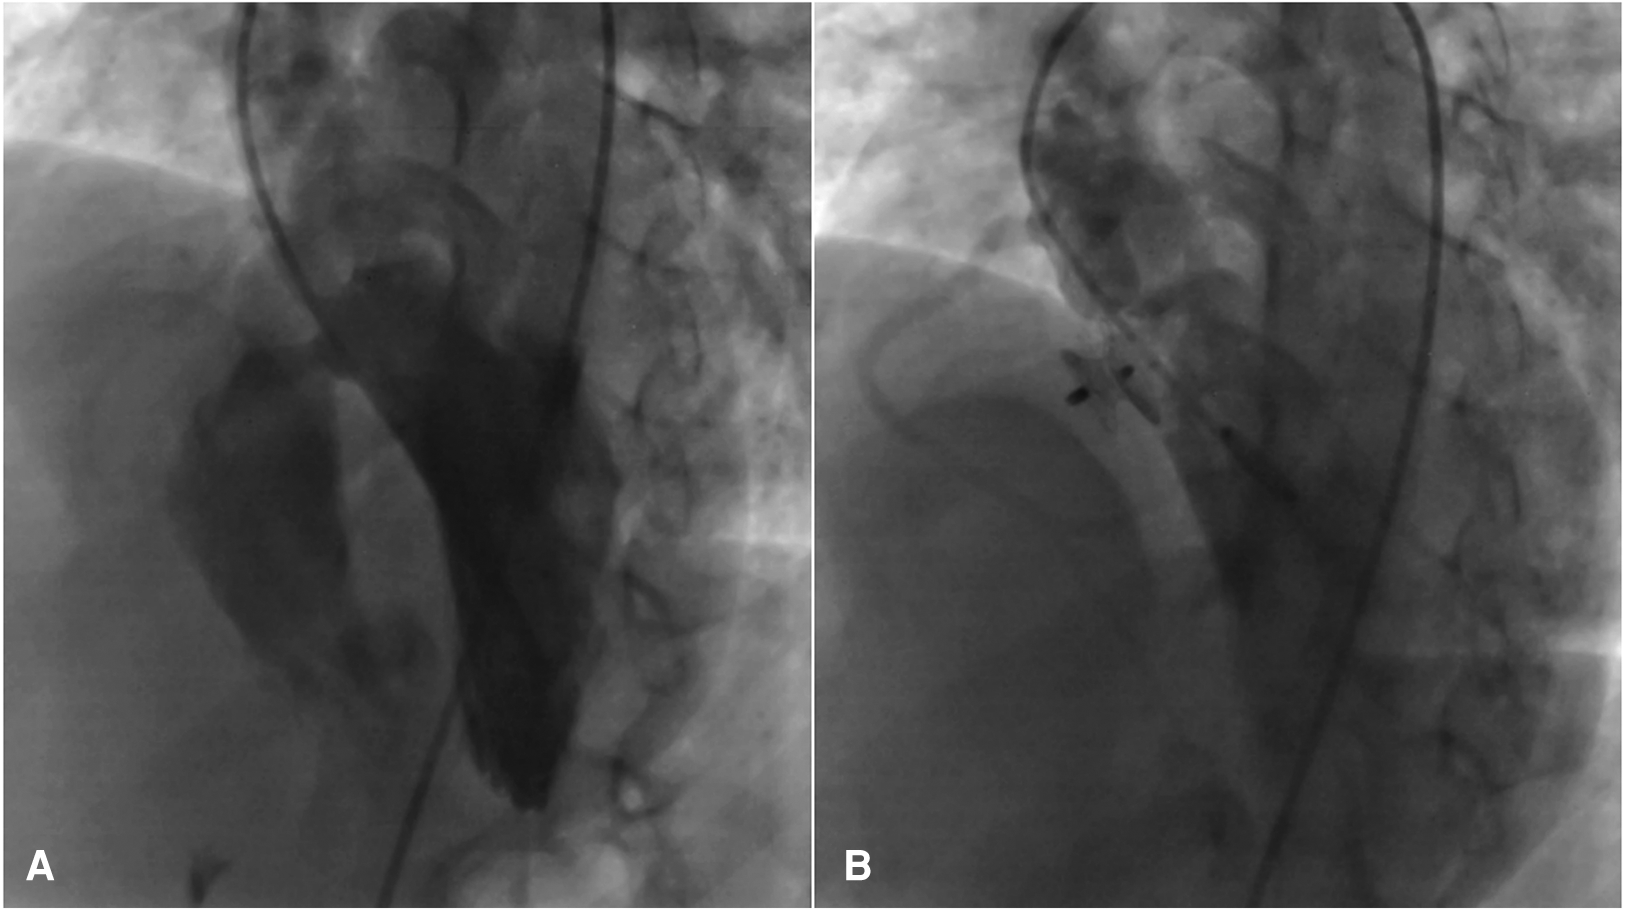

Figure 3

Significant peri membranous VSD extended to the sub-aortic septum, for which the 4D flow image was also displayed in (A), that was occluded by an 8 mm amplatzer asymmetric septal occluder (B).